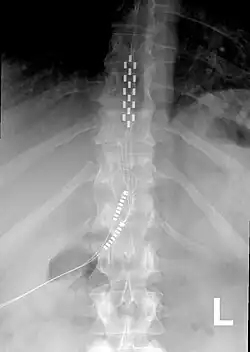

![]() Anterior view X-ray of a spinal cord stimulator (SCS) implanted in the thoracic spine |